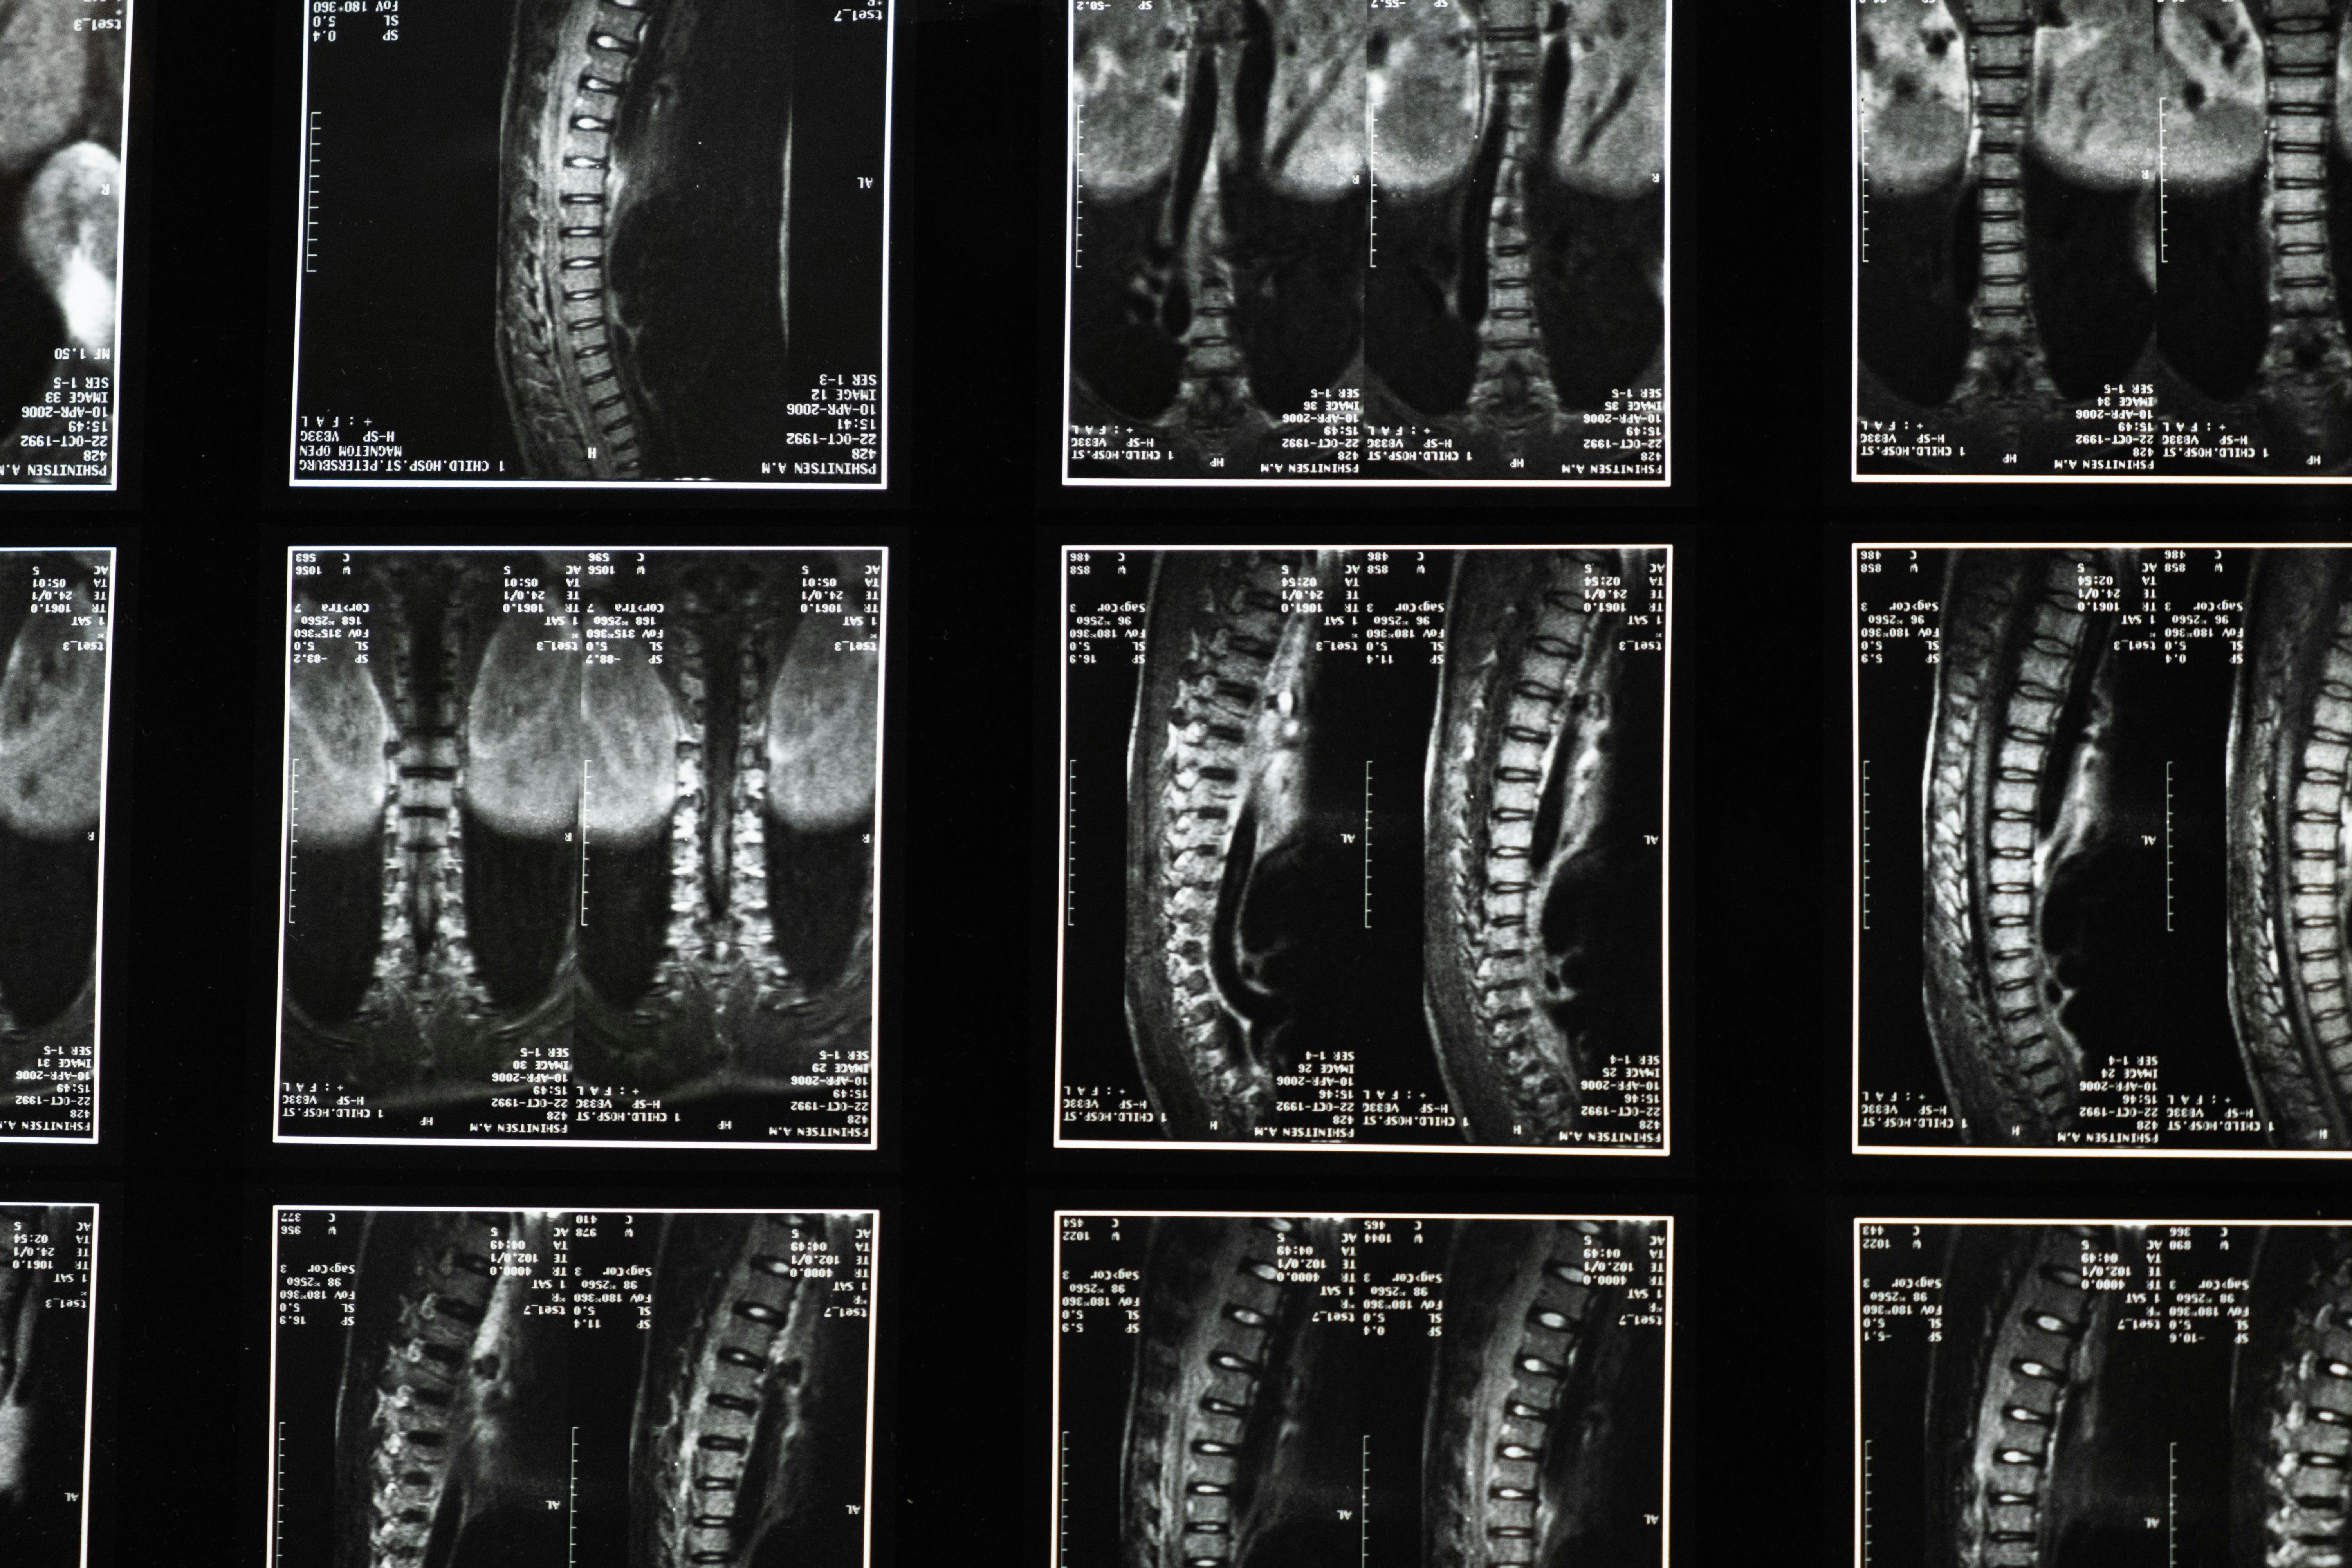

진단

골밀도 검사를 통해 티 수치(T-scores)로 판단합니다. 수치가 -1 이상이면 정상입니다. -1~-2.5 사이면 골감소증으로 분류합니다. 수치가 -2.5 이하일 경우 골다공증으로 분류합니다. X-ray검사를 진행하여 골다공증으로 인한 압박 골절 등이 있는지 알 수 있습니다.